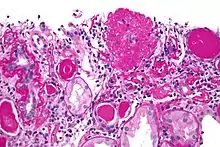

Micrograph of the collapsing variant of FSGS (collapsing glomerulopathy). A collapsed glomerulus is seen at the top, right-of-centre. PAS stain. Kidney biopsy.

Histopathology of collapsing glomerulopathy. (A,B) Periodic Acid Schiff (PAS) and Jones Methenamine Silver (JMS) (40×), respectively show intense podocyte hyperplasia and glomerular tuft collapse. (C) JMS (20×) exhibits microcytic transformation of distal convoluted tubules with accumulations of hyaline material inside of those. (D,E) Fluorescence microscopy (40×) shows, respectively, IgM and C3 trapping in areas of collapse/sclerosis. (F) Semi-fine stained in Toluidine Blue (63×) with collapse of the entire glomerular tuft and hyperplasia of podocytes and dilated Bowman's space. (G,H) Transmission electron microscopy contrasted with Osmium Tetroxide, Lead Citrate and Uranyl in block shows capillary loop collapse with hyalinosis in addition to diffuse fusion and flattening of the pedicels associated with microvillous transformation. (I) Electron microscopy tubes contrasted with osmium tetroxide, lead citrate, and uranyl in block with detail of disorganization of the cytoskeleton in the podocyte cytoplasm, with extensive effacement of the pedicels.[33]

Five mutually exclusive variants of focal segmental glomerulosclerosis may be distinguished by the pathologic findings seen on renal biopsy:[34]

1. Collapsing variant

2. Glomerular tip lesion variant

3. Cellular variant

4. Perihilar variant

5. Not otherwise specified (NOS) variant.

Recognition of these variants may have prognostic value in individuals with primary focal segmental glomerulosclerosis. The collapsing variant is associated with higher rate of progression to end-stage renal disease, whereas the glomerular tip lesion variant has a low rate of progression to end-stage renal disease in most patients.[9] The cellular variant shows similar clinical presentation to collapsing and glomerular tip variant but has intermediate outcomes between the other two variants.[9]